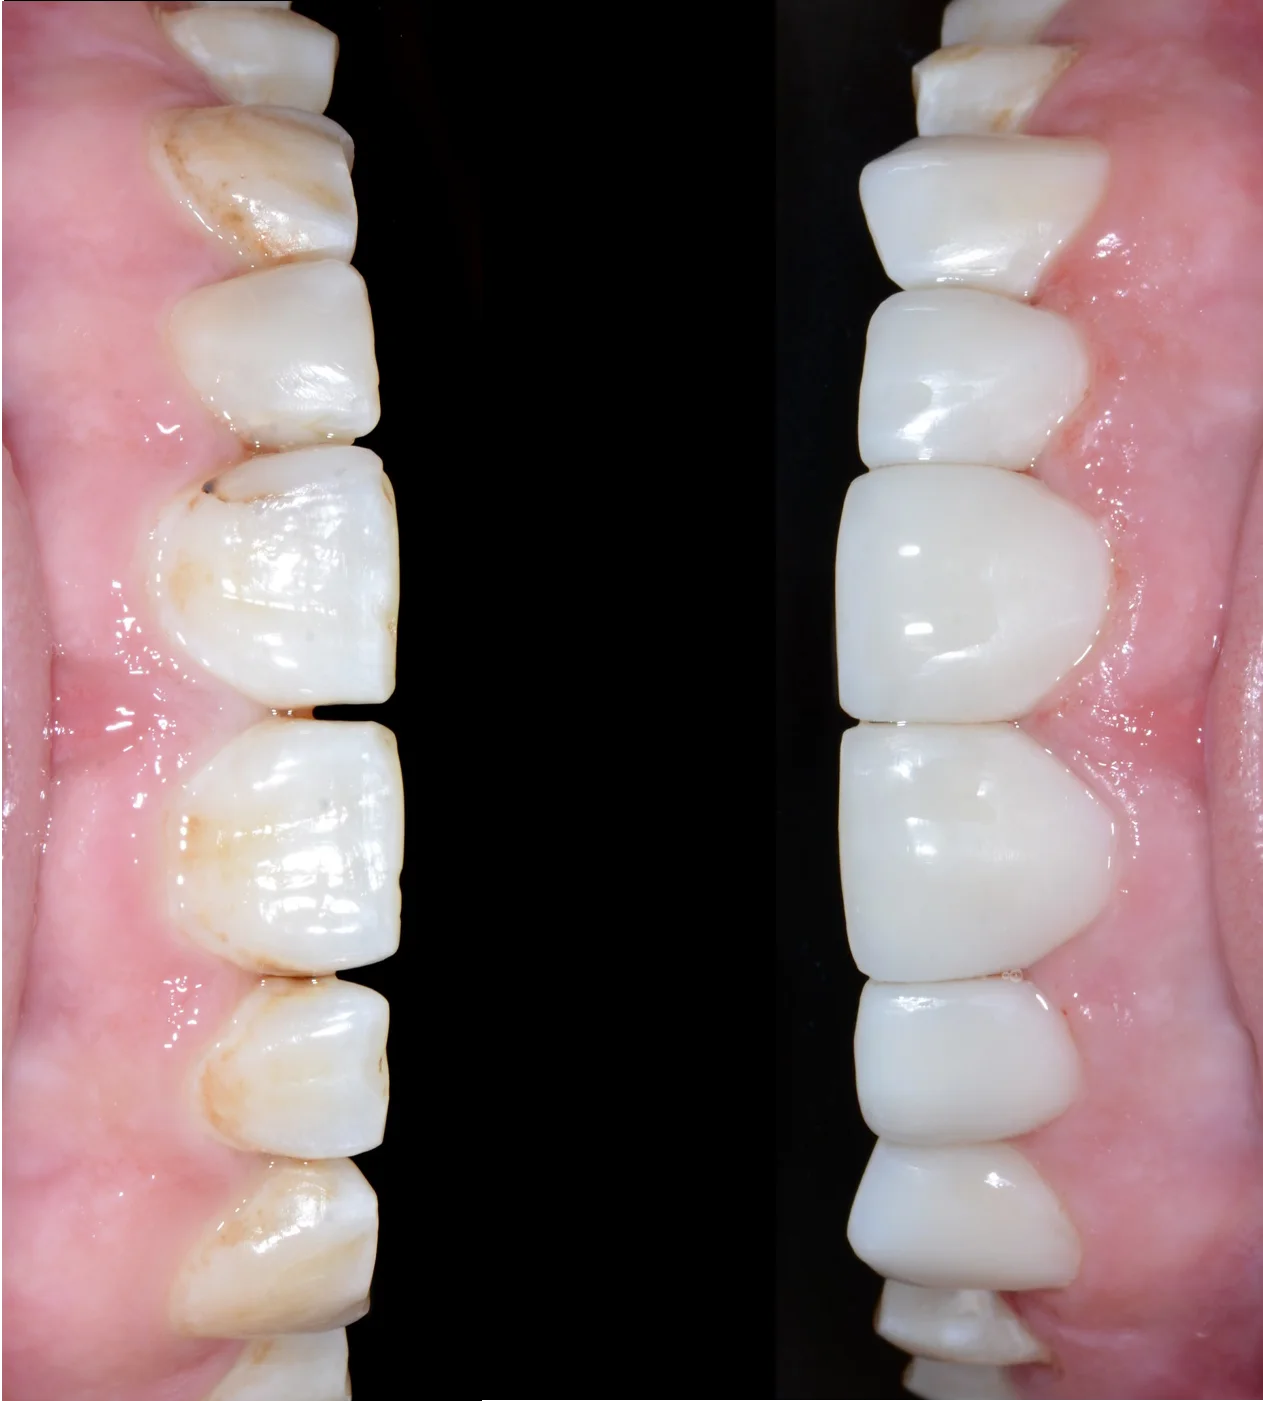

Художня Реставрація зубів

Фаховий лікар-реставратор проводе лікування з використанням мікроскопа, фотопротокола та цифрового прогнозу майбутньої ідеальної посмішки пацієнта. Використовуються лише сучасні пломбувальні матеріали.

06 Я хочу змінити форму та колір моїх зубів. Чи можливо це?

Так. Лікар проводить художню реставрацію зубів із застосуванням мікроскопа, цифрового прогнозування та сучасних пломбувальних матеріалів для досягнення естетичного результату.